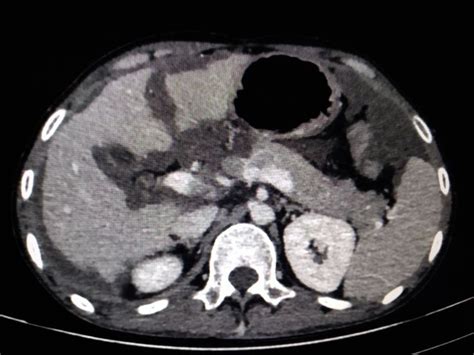

Alright folks, let’s talk about the symptoms and diagnosis of Pseudomyxoma Peritonei (PMP) . This is where things can get a little tricky because, honestly, PMP often likes to play hide-and-seek. The symptoms can be super vague and develop very slowly over months or even years. This is why it’s often misdiagnosed or diagnosed quite late. One of the most common complaints is a gradual increase in abdominal size or bloating . You might feel like your pants are getting tighter, or your belly just feels full and distended. This is due to the accumulation of that characteristic mucinous material within the abdominal cavity. Some people describe it as feeling like they’ve gained a lot of weight rapidly, but it’s not fat – it’s the gel-like substance. Abdominal pain or discomfort is another frequent symptom. This pain can be dull, achy, or sometimes sharp, and it might worsen as the abdomen becomes more distended. It can also be related to pressure on nearby organs. Changes in bowel habits are also common. This could mean constipation, or sometimes diarrhea, or just a general feeling that things aren’t moving smoothly in your gut. Because the mucus can build up and potentially block parts of the intestines, bowel obstruction is a serious complication that can occur. Nausea and vomiting can also be signs, especially if there’s significant obstruction. Other less specific symptoms can include fatigue, loss of appetite, or unintended weight loss, though weight gain due to abdominal distension is more common. So, how do doctors figure out what’s going on? The diagnostic journey for PMP usually involves a combination of methods. Imaging tests are super important. A CT scan (Computed Tomography) of the abdomen and pelvis is often the first step. It can show the characteristic widespread distribution of the mucinous material and any tumors. Sometimes, an MRI (Magnetic Resonance Imaging) might be used for more detailed views. Ultrasound can also be helpful, especially in identifying ovarian masses. However, imaging alone can’t always give a definitive answer. Blood tests are usually done, but there aren’t specific tumor markers that reliably diagnose PMP. The most crucial step for a definitive diagnosis is a biopsy . This involves taking a sample of the tumor tissue or the mucinous fluid from the abdomen. This sample is then examined under a microscope by a pathologist to confirm the presence of mucinous adenocarcinoma cells and determine their origin. Sometimes, the diagnosis is made during surgery when doctors are investigating the cause of the abdominal symptoms. It’s a challenging condition to diagnose because the symptoms mimic so many other common issues, like irritable bowel syndrome, ovarian cysts, or even simple indigestion. That’s why it’s vital for healthcare providers to consider rarer conditions, especially when symptoms are persistent or unusual. The key takeaway is to listen to your body. If you’re experiencing persistent abdominal distension, pain, or changes in your bowels that don’t have a clear explanation, don’t hesitate to seek medical attention. Early diagnosis, while challenging, can significantly impact treatment outcomes for PMP.